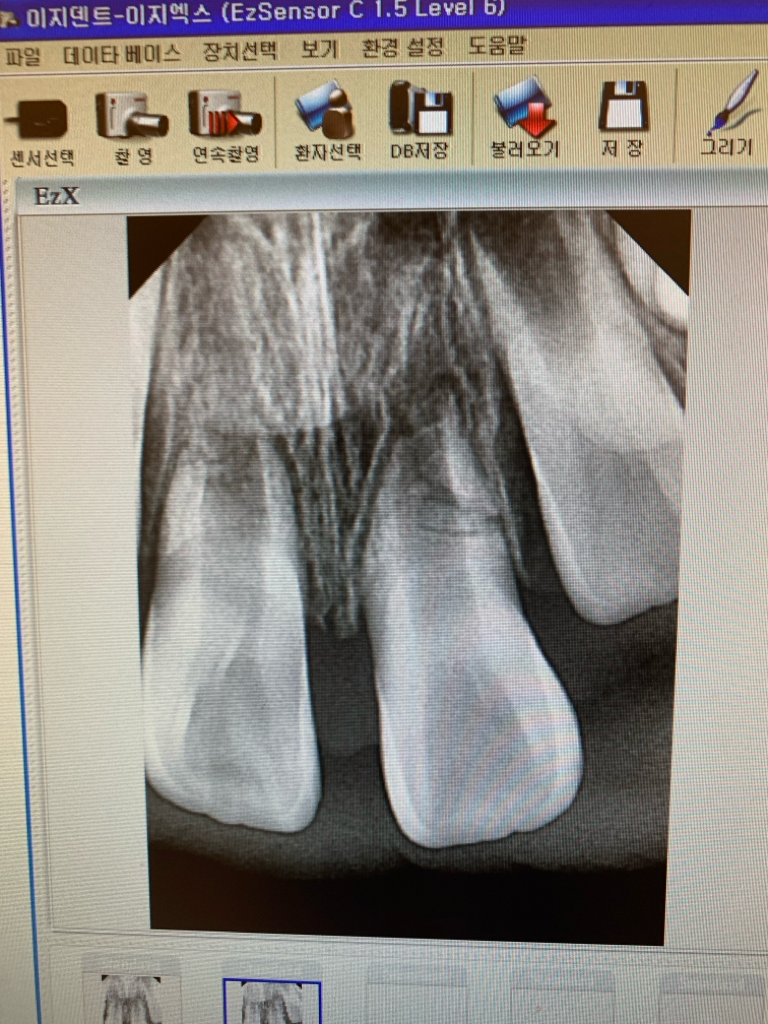

중절치 수평치근파절 예후가 궁금합니다.

아이가 6월 친구가 덮쳐 넘어져 바닥에 이를 부딪혀서 중절치 치근이 파절되었습니다.

이틀전 치과검진에서 엑스레이 검사후 두 치아 다 신경이 온전해서 치아 파절편 사이를 치아 뿌리 만드는 세포들이 와서 붙여주는거 같다고 길게 말씀을 해주셨어요,

아직 뿌리가 다 완성되지 않은 맹출중인 치아이니

계속 지켜보자고 말씀을 하셨어요,

처음 다쳤을때 사진이고 최근 사진은 없습니다..

• 1번 째 사진

해당부위 수평파절은 치아 뿌리쪽 파절이기 때문에 특별히 치과에서 치료를 해줄 것은 없습니다. 외상 당시 치아가 흔들렸다면 1~2주 정도 옆 치아와 고정은 해줄 수 있습니다만 지금은 시기가 지나지 않았나 싶습니다.

아직까지 현재 치아는 치근단공이 닫히지 않은 (뿌리끝까지 다 형성되지 않은) 미성숙영구치 입니다. 미성숙 영구치는 회복이 빠른 장점도 있으니 기다리는 수밖에 없습니다.

일단은 기다려 보시는게 좋을것같습니다. 저정도 파절선이 보이는경우라면 예후가 좋아 보이진 않습니다.